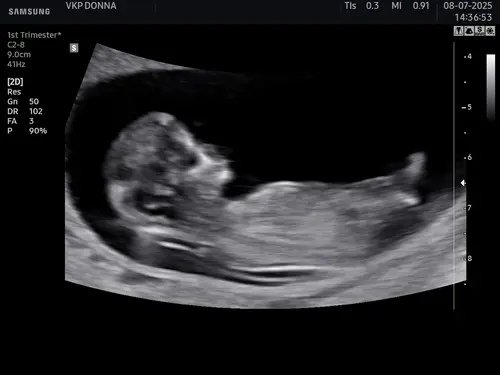

Wat denken jullie 馃┑馃┓